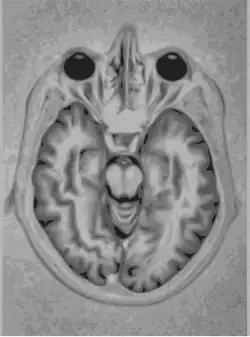

- Ressonância Magnética

Ressonância Magnética (MRI) é uma tecnologia de imagem médica que usa ondas de rádio e um campo magnético para criar imagens detalhadas de órgãos e tecidos. MRI provou ser altamente eficaz no diagnóstico de uma série de condições, mostrando a diferença entre normais e doentes tecidos moles do corpo. A RM é frequentemente utilizada para avaliar:

- Veias de sangue

- Tecido anormal

- Peito

- Ossos e articulações

- Órgãos na pelve, tórax e abdômen (coração, fígado, rim, baço)

- Lesões na coluna

- Rasgos do tendão e do ligamento.[7]

- Ressonância Magnética

A Ressonância Magnética Nuclear (RMN) utiliza ímãs potentes para polarizar e excitar os núcleos de hidrogênio (prótons individuais), que são amplamente encontrados no tecido humano. O scanner usa antenas para produzir pulsos de ondas de rádio na frequência de ressonância dos átomos de hidrogênio nas moléculas de água. As ondas de rádio geradas em resposta são codificadas e resultam em imagens do órgão desejado.[9]

Nas técnicas com raio-X, apenas os tecidos densos criam boas imagem, sendo muito difícil avaliar tecidos pouco densos como o tubo digestivo e o sistema reprodutor. Assim, pode ser usado para investigar tumores, o fluxo de sangue do coração, função renal e função pulmonar.